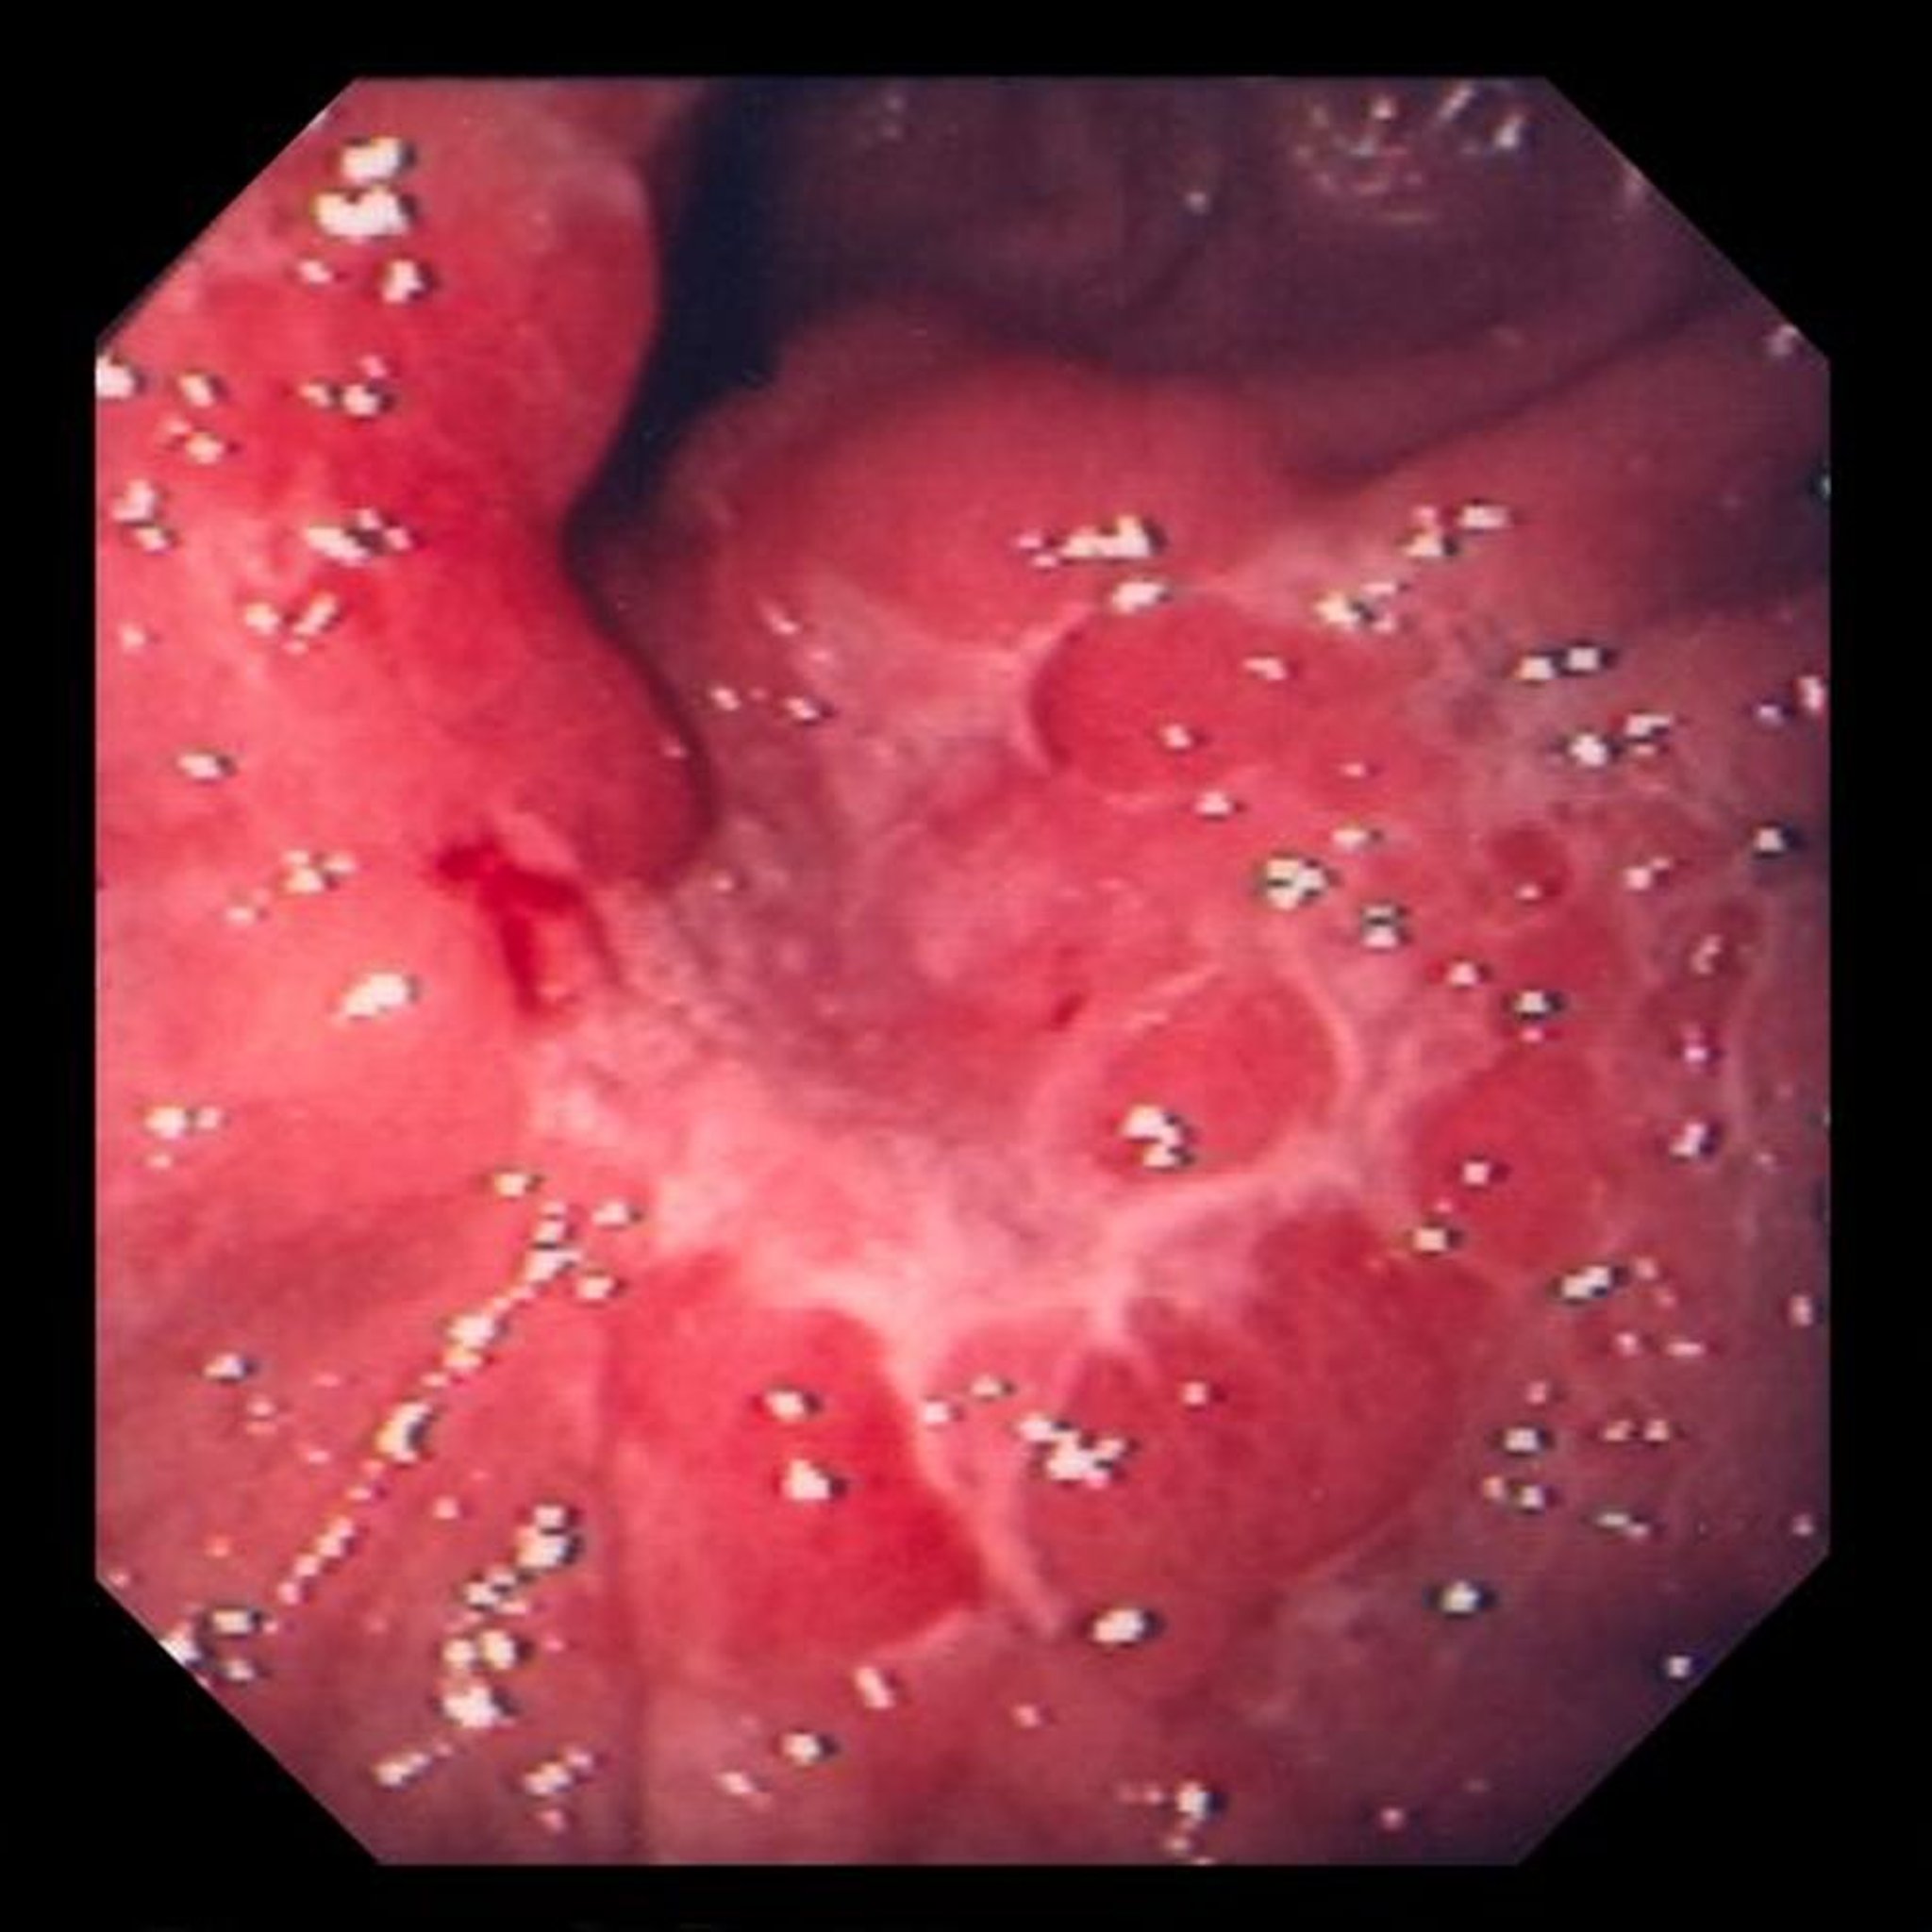

Hình ảnh này cho thấy một vết loét trong nếp gấp niêm mạc phù nề, trên sinh thiết kết quả là ung thư biểu mô tuyến biệt hóa kém (loại tế bào vòng dấu hiệu).

Hình ảnh do bác sĩ David M. Martin cung cấp.